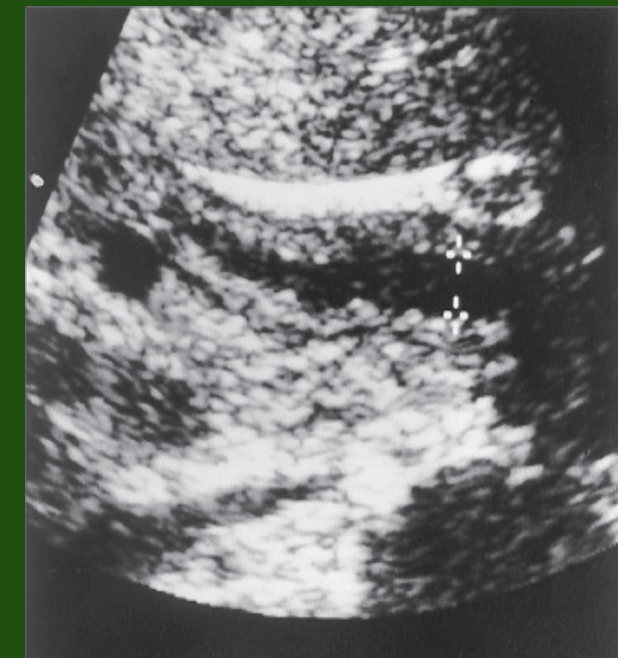

Inflammation of the pancreas may cause the common duct to dilate. This patient has acute pancreatitis (P) and dilation of the common duct (crossbars).

A, Aorta; IVC, inferior vena cava.